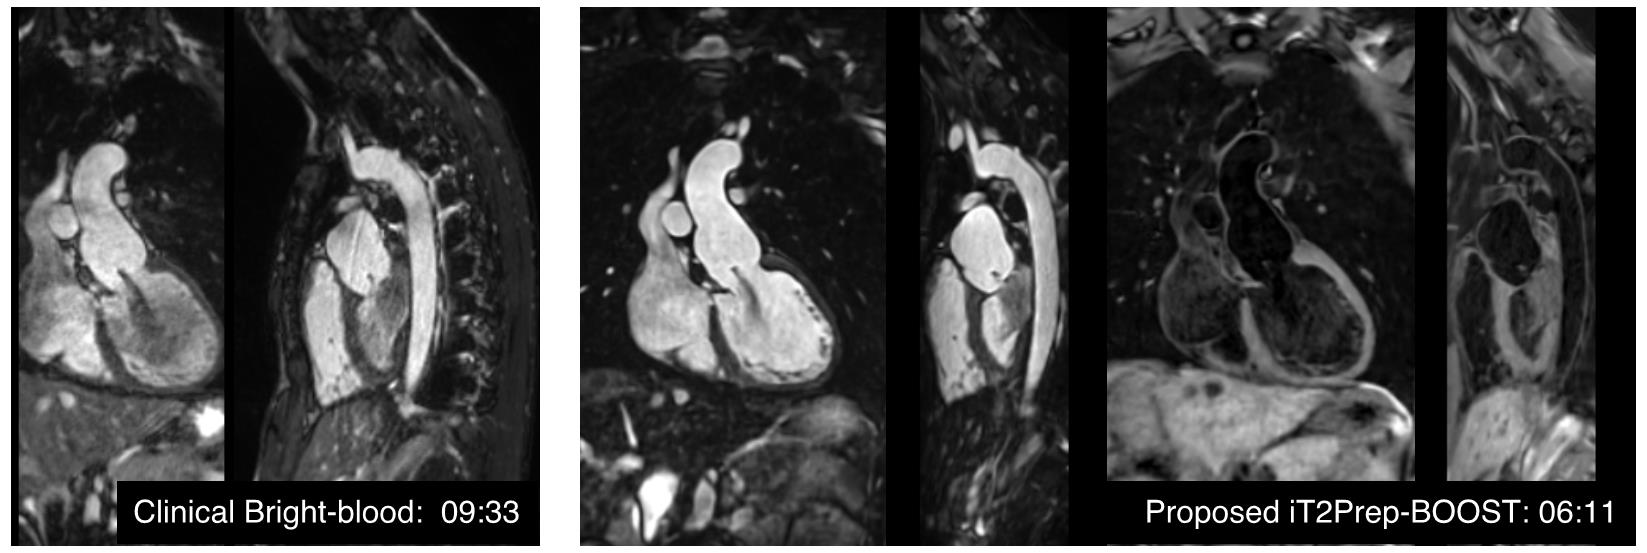

iT2Prep-BOOST を aortic lumen + vessel wall へ展開。

2025

Hajhosseiny

NSTEMI culprit / vulnerable plaque assessment。PMR 議論の臨床translation。